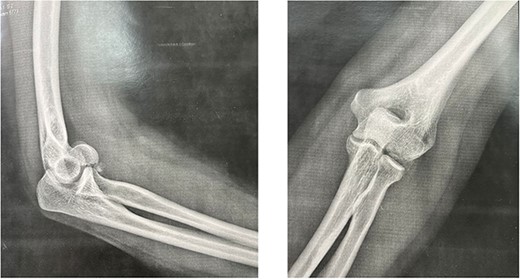

This is a prospective, monocentric study of adult patients undergoing surgical treatment for isolated capitellar fracture. Between 2019 and 2022, we received eight patients (six men and two women) with a mean age of 25 years (18–40 years) who had type I fracture of the capitellum. The dominant arm was affected in six patients (Table 1). All our patient had a fall on an outstretched hand. All fractures were close and isolated without any vascular or neurological damage. Standard AP (anteroposterior), lateral X-rays (Fig. 1) as well as a computed tomography (CT) scan with 3D reconstruction were done for all the patients (Fig. 2). Therefore, fractures with trochlea involvement were excluded.